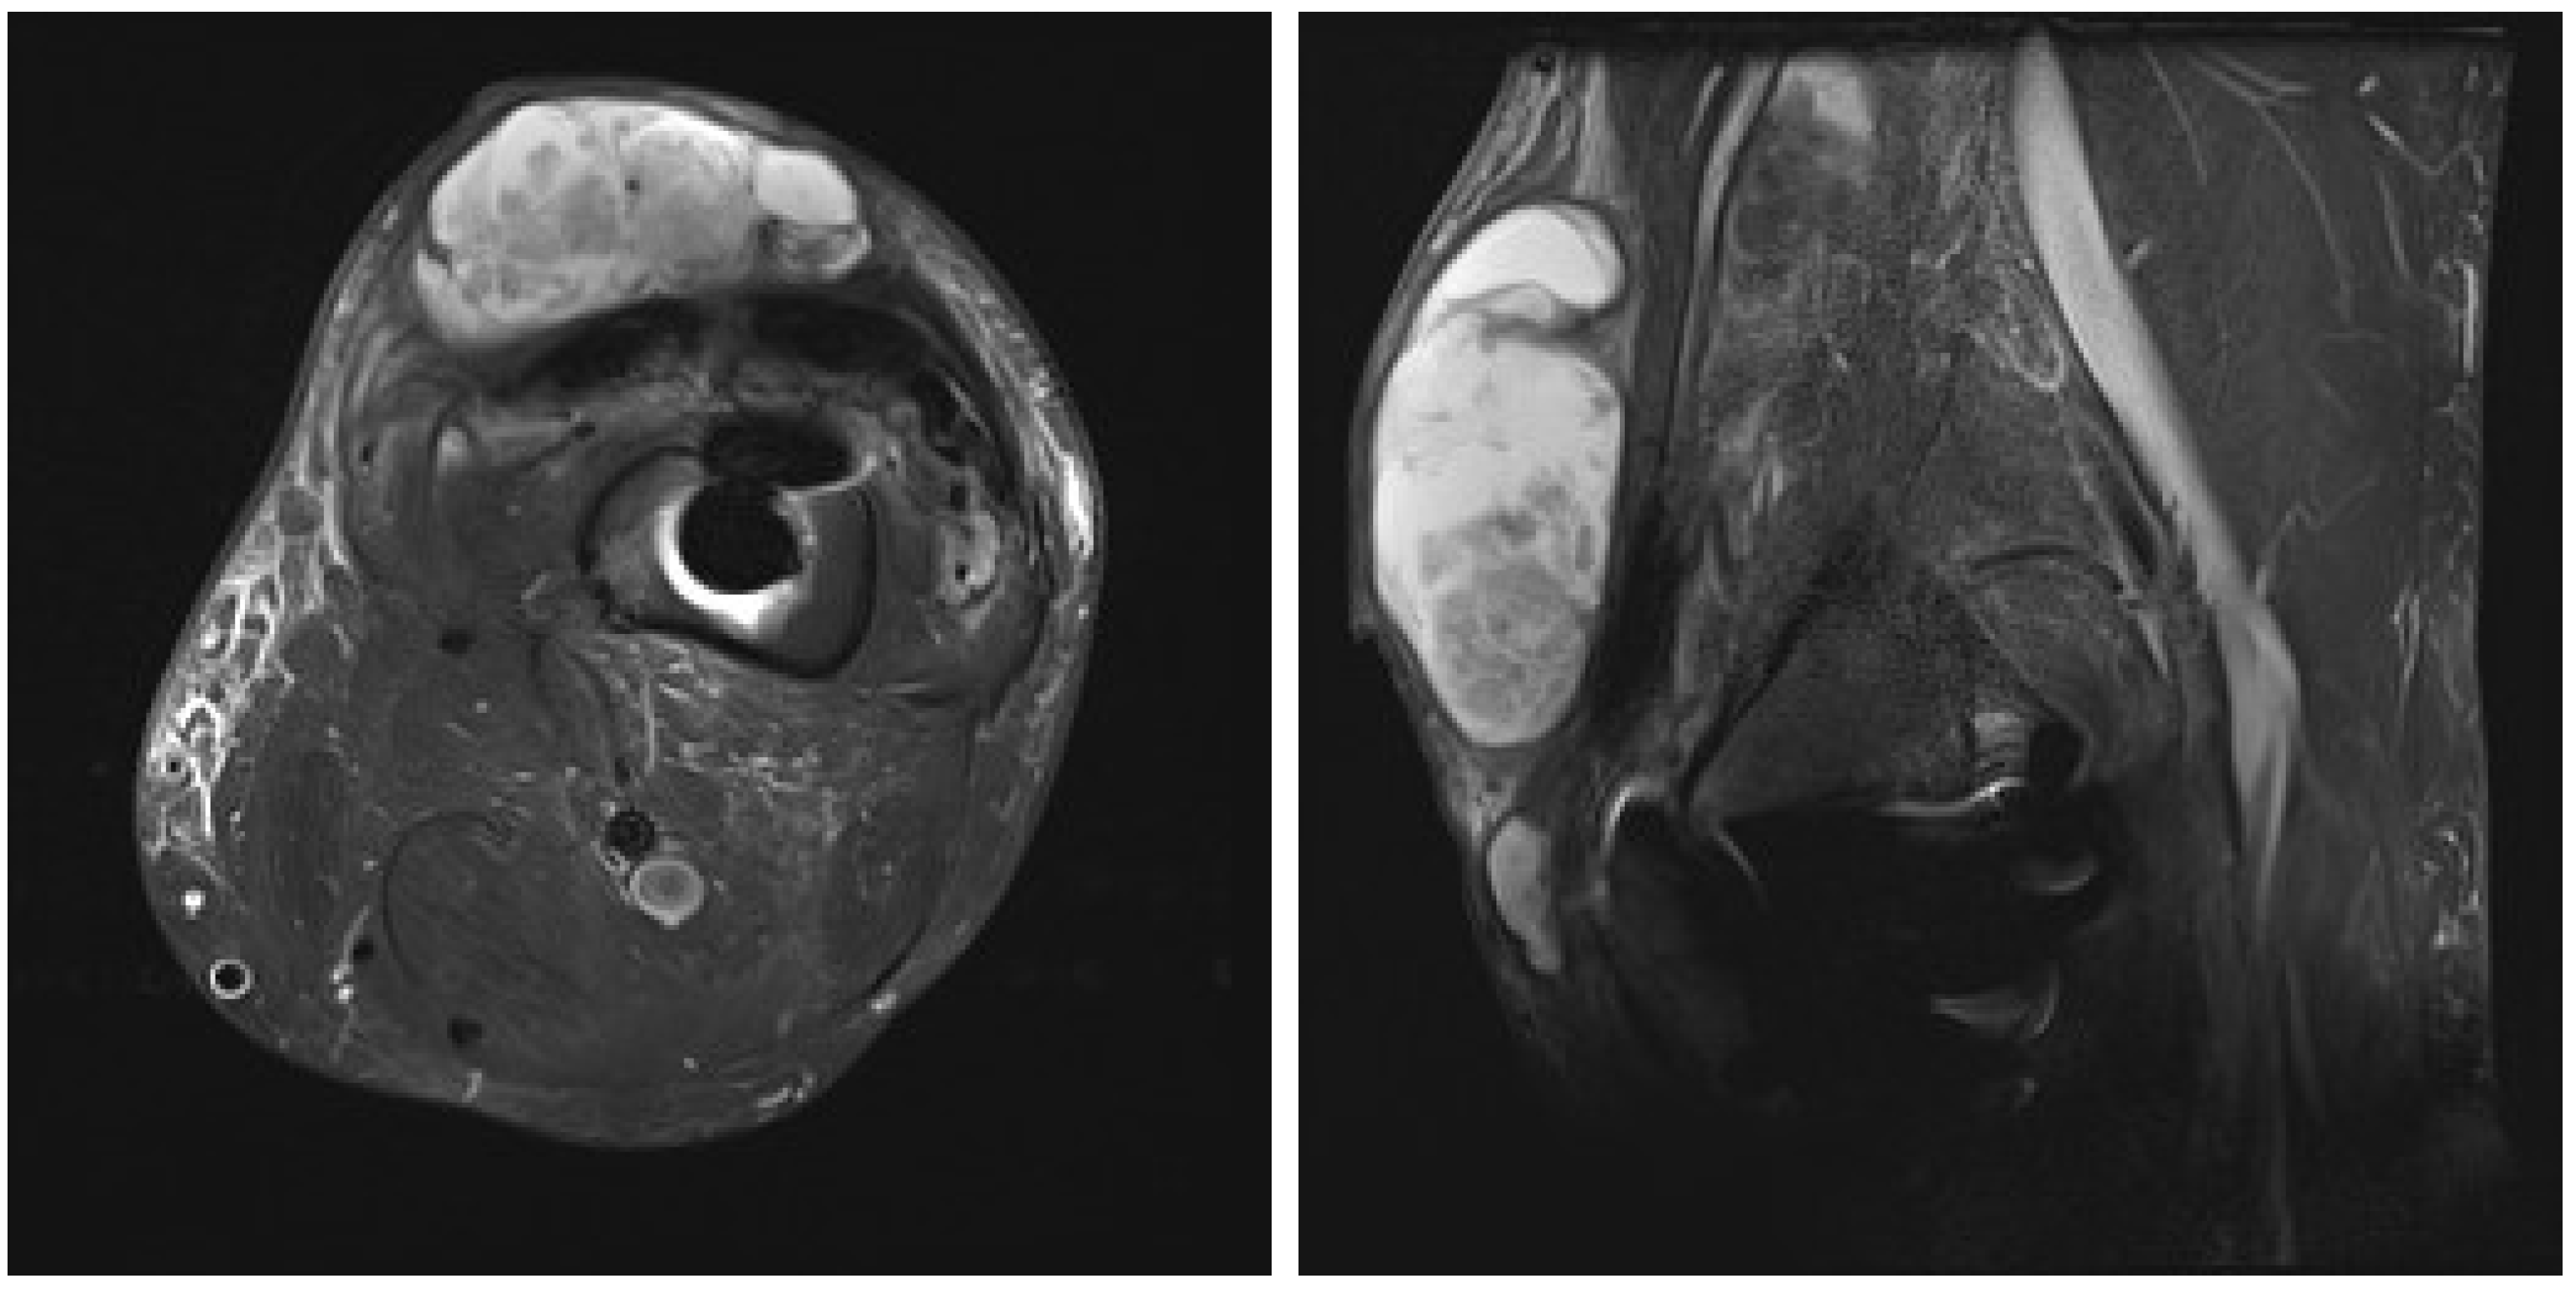

After an uneventful period of seven months, the patient was admitted in September 2024 with left knee pain, prepatellar swelling, and redness of the skin, without any systemic signs of infection. Laboratory tests revealed a normal complete blood cell count and an elevated C-reactive protein (CRP) level of 93 mg/dL. A high suspicion of PJI was established, and knee aspiration was performed twice in September 2024, with the samples sent to the microbiological laboratory. Laboratory analysis of the knee aspiration showed elevated leucocyte count in synovial fluid, with a differential cell count revealing 91% neutrophil granulocytes, total protein concentration of 44 g/L, consistent with an inflammatory process. Contrast-enhanced magnetic resonance imaging (MRI) of the left knee was performed, showing pronounced synovitis intra-articular with a small effusion extending through the defect of the quadriceps tendon just above the patella into the subcutaneous tissue suprapatellar into a large septate collection (Figure 2).

Figure 2. Contrast-enhanced magnetic resonance image of left knee: axial and lateral view of the left knee showing pronounced synovitis intra-articular with a small effusion, extending through the defect of the quadriceps tendon just above the patella into the subcutaneous tissue suprapatellar, forming a large septate collection, small osteolysis around the femoral part of knee endoprosthesis.